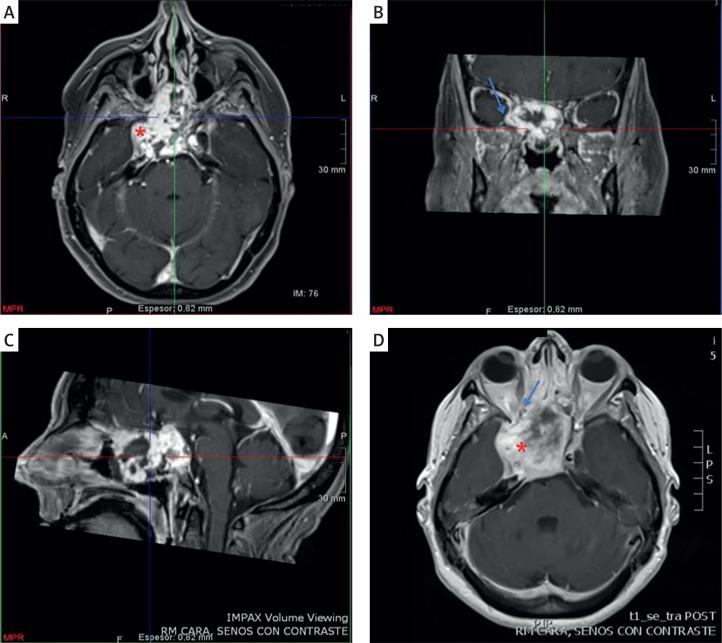

Epithelioid haemangioendothelioma (EHE) is a rare low-grade vascular neoplasm that is composed of mostly epithelioid cells. EHE may arise as a solitary tumour or in the form of multiple body lesions, and commonly occurs in soft tissues, liver, pleura, lung, peritoneum, lymph nodes, breast, and many other sites. EHE in the cranionasal region is extremely rare. There are very few reports of cases of skull-base EHE. We discuss an extremely rare presentation of an aggressive EHE that originated from the sellar region. Based on literature review, our patient is the first reported case of a giant solitary EHE with prepontine cistern invasion and abducens nerve encroachment mimicking a chondrosarcoma. We treated this rare tumour by near subtotal surgical excision with subsequent radiotherapy, considering that complete tumour resection with free margins in both cavernous sinus and clival region avoiding neural and vascular structure encroachment becomes technically difficult.

上皮样血管内皮瘤(EHE)是一种罕见的低级别血管肿瘤,主要由上皮样细胞组成。EHE可表现为孤立性肿瘤或多发性全身病变,常见于软组织、肝脏、胸膜、肺、腹膜、淋巴结、乳腺及许多其他部位。颅鼻区域的EHE极为罕见。关于颅底EHE的病例报道非常少。我们讨论了一例起源于鞍区的侵袭性EHE的极其罕见的病例。基于文献回顾,我们的患者是首例报道的巨大孤立性EHE,侵犯脑桥前池并压迫展神经,酷似软骨肉瘤。考虑到在海绵窦和斜坡区域实现肿瘤完整切除且切缘阴性,同时避免侵犯神经和血管结构在技术上具有难度,我们对这例罕见肿瘤进行了近全手术切除并随后进行放疗。